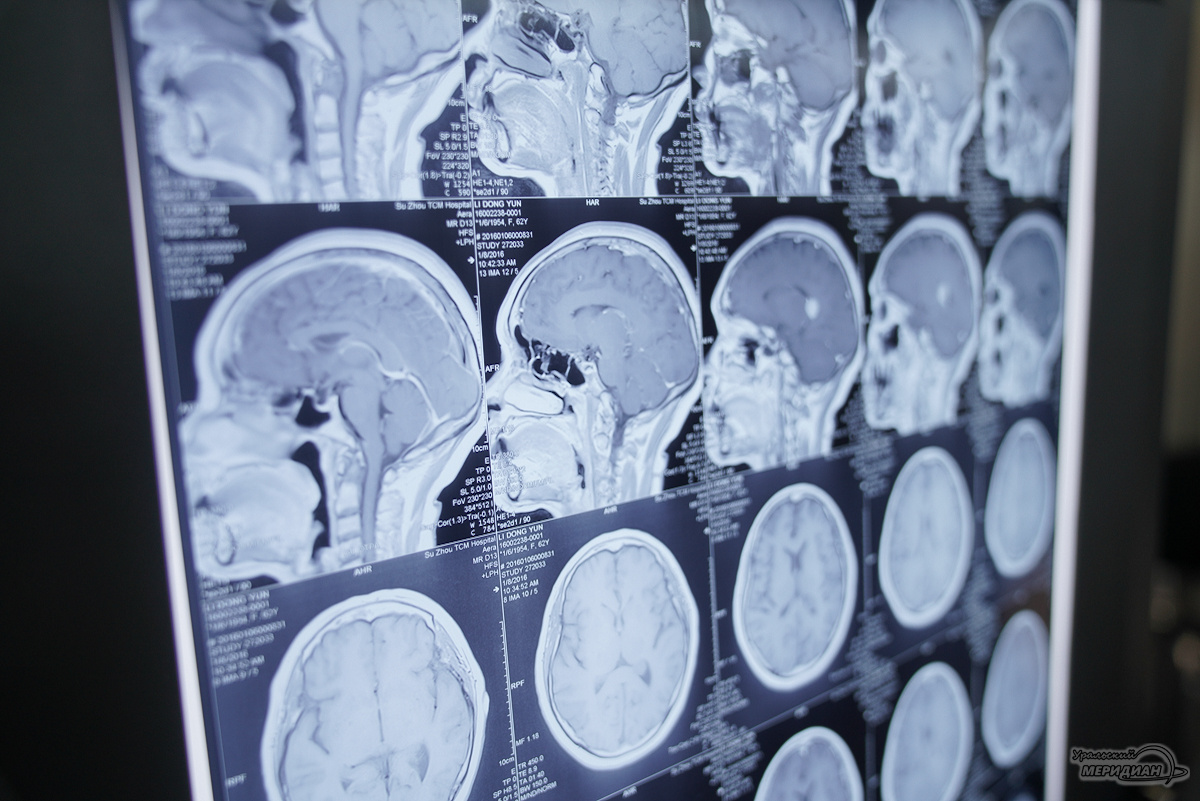

Специалисты областного онкологического диспансера спасли жизнь мужчине с огромной менингиомой крыла клиновидной кости, которая повредила череп. Об этом случае спасения сообщили в министерстве здравоохранения Свердловской области.

Менингиома — одна из самых распространённых доброкачественных опухолей мозга, способная вызывать серьёзные нарушения слуха, зрения, речи, чувствительности и двигательной активности. Без своевременного лечения она представляет угрозу жизни пациента.

Пациент из Краснотурьинска с таким диагнозом поступил в отделение нейроонкологии. Как рассказал нейрохирург Свердловского областного онкодиспансера Павел Гвоздев, опухоль уже выросла до размеров примерно 15 на 15 сантиметров и проросла наружу через кости черепа на 10 сантиметров. При этом мужчина не испытывал симптомов и затруднился объяснить, почему долго не обращался за помощью.

Лечение прошло в два этапа. Прежде всего, рентгенэндоваскулярные хирурги провели малоинвазивную операцию по закупорке сосудов, питающих опухоль, чтобы снизить риск кровотечения. И затем нейрохирурги удалили менингиому, отделив её от мозга. Они восстановили оболочку и крупную вену, установили титановую сетку для протезирования черепа и провели пластику кожи для восстановления анатомической формы. Операция длилась около 7 часов и прошла успешно. Врачи отметили благополучное восстановление пациента.